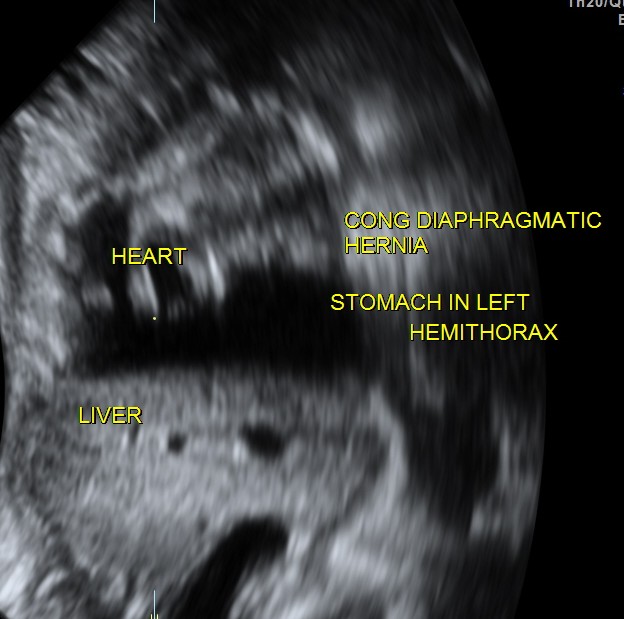

This was a 23 year old primi gravida without history of consanguinity was sent for anomaly scan at 33 weeks of gestation. Earlier two scans had not detected any anomaly at another centre.

The heart was seen in the right side of thorax . The left hemithorax showed the stomach bubble and bowel loops suggestive of Congenital Diaphragmatic Hernia .